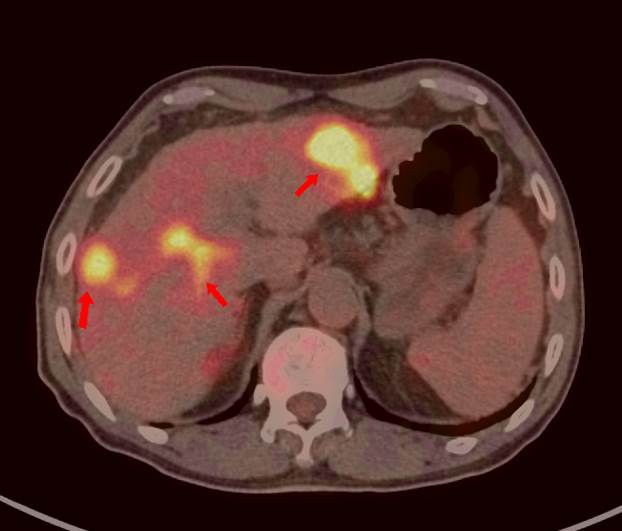

69歲王老伯,發(fā)現(xiàn)肝占位2月余,口服靶向藥物治療,近期外院CT發(fā)現(xiàn)肝多發(fā)占位,診斷為肝細(xì)胞肝癌并肝內(nèi)轉(zhuǎn)移,查血腫瘤標(biāo)記物,AFP 5410ng/ml,有乙肝病史。

PET/CT顯示肝臟左右葉內(nèi)多發(fā)大小不等稍低密度結(jié)節(jié),最大病灶5.8x5.5cm,密度不均,F(xiàn)DG攝取不同程度最高,SUVmax3.9-9.6,門靜脈右支增寬,F(xiàn)DG攝取最高,SUVma 4.9。

PET/CT診斷:原發(fā)性肝細(xì)胞肝癌 (多發(fā)結(jié)節(jié)型)并壞死、出血、門靜脈右支癌栓形成;肝硬化